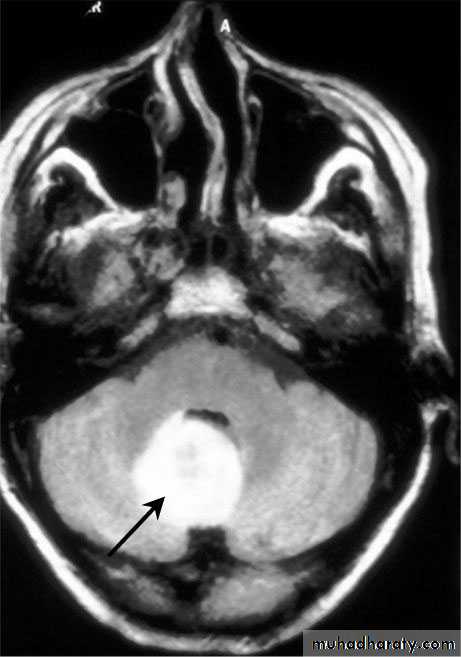

Cerebellar Abscess

• Indications for Excision (Craniotomy):

• Cerebellar Abscesses.